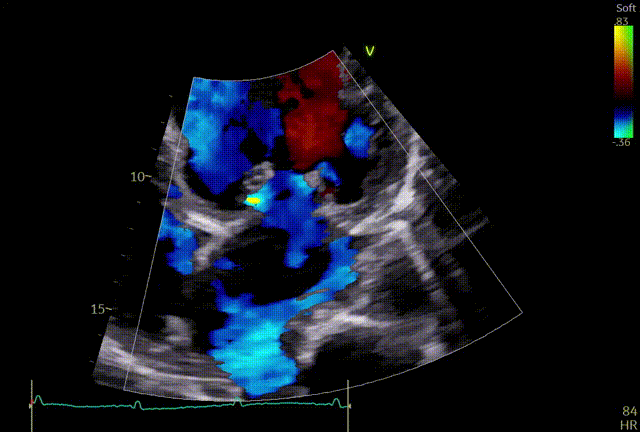

释放后

外侧2偏1区可见后叶栓系,下方空间乳头肌腱索杂多,后叶长度也一般,跨瓣压差3mmHg,第三枚夹子选择了NT,打算靠近第一枚夹子2偏1区夹持,置入NT后,在1区上方做轨迹测试,充分释放张力,调整夹子的夹臂方向位于1点-7点的方向,回拉系统,使第三枚夹子靠近第一枚夹子,关小夹子进入到心室侧,由于第一枚夹子起到了稳定瓣叶的作用,第三枚夹子捕捞夹持相对顺利,一次精准捕获前叶和后叶,再次完整评估二尖瓣NT的方向、组织桥稳定性、瓣叶受限程度及反流减小程度。反流改善到1+-2+,平均跨瓣压差3.85mmHg,左房压明显下降,肺静脉逆流明显改善,手术完美结束。

最终结果

术后肺静脉频谱

术后平均跨瓣压差

术后左房压